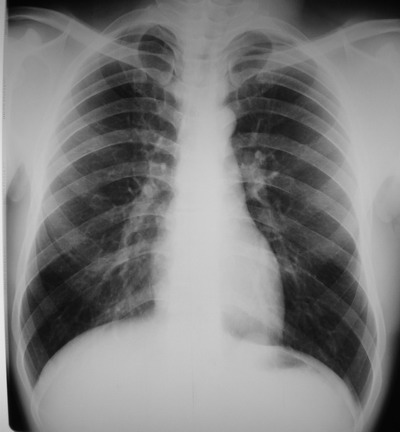

以下是引用余辉在2007-6-16 20:47:00的发言:[br]图像不边续,1左肺下叶膈后囊性病灶,与胃有密切联系,考虑局限性膈膨隆,不排除其他如脓肿等;2左膈肌脚增厚,其前方肝胃间隙内可见球形病灶,左肾上腺病变?进一步检查